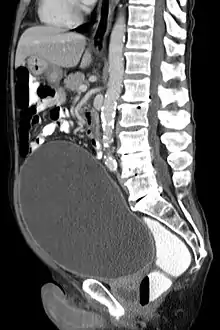

| CT scan in the sagittal plane which reveals a greatly enlarged urinary bladder caused by urinary retention, a condition which often leads to overflow incontinence. | |